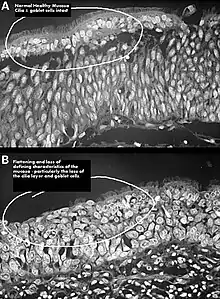

One possible cause may be changes to the nasal mucous membrane and to the nerve endings in the mucosa resulting from chronic changes to the temperature and humidity of the air flowing inside the nose, caused in turn by removal or reduction of the turbinates.[3][5] Direct damage to the nerves may be a result of surgical intervention; however, as of 2015, there is no technology that allows the mapping of the sensory nerves within the nose, so it is difficult to determine whether this is causative of ENS.[3] Investigators have been unable to identify consistent diagnostic or precipitating features, psychological causes leading to a psychosomatic condition have been proposed.[3][9][10][12]